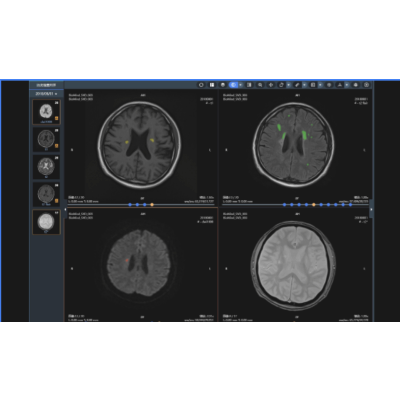

脑小血管病辅助决策

脑小血管病是缺血性卒中、出血性卒中、认知损害和抑郁的发病重要诱因,利用MR影像数据,评估脑小血管病负荷,判定病因或者预估未来卒中发病风险具有重要意义,安德医智BioMind产品能够高速完成病变的精确分割和性质判定,实现脑小血管病的精确定性诊断和定量评估。